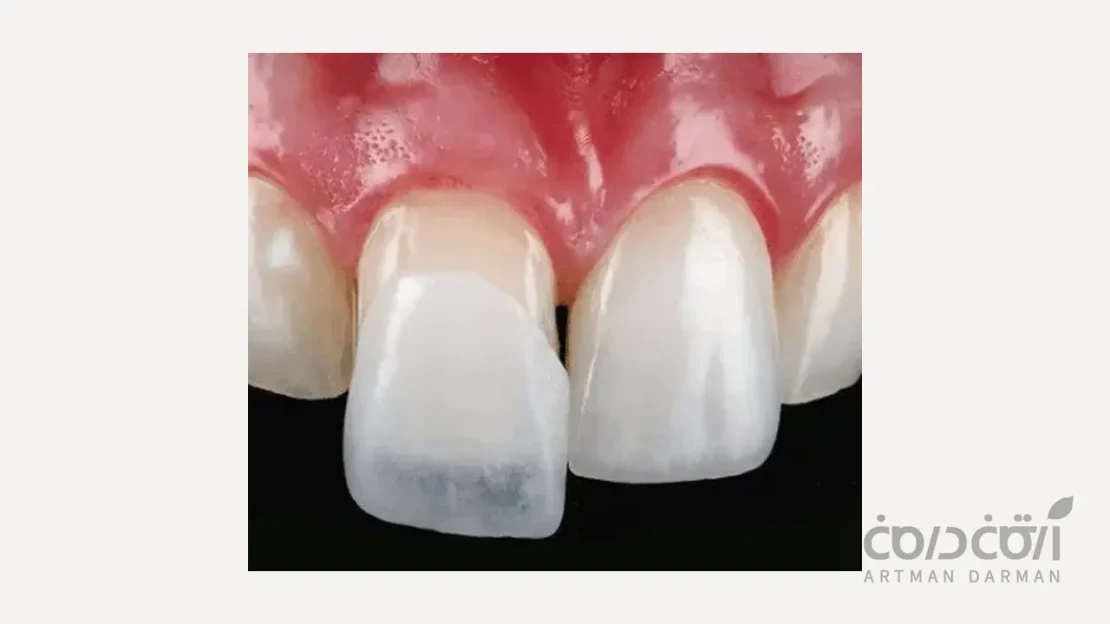

فرآیند تراش دندان برای لمینت، یک مرحله دقیق و کنترلشده است که با هدف حفظ حداکثری بافت سالم دندان انجام میشود. در نخستین گام، دندانپزشک پس از بررسی طرح لبخند و تعیین شکل نهایی لمینت، میزان تراش مورد نیاز را با دقت مشخص میکند. سپس با استفاده از ابزارهای ظریف، لایهای بسیار نازک از مینای سطح جلویی دندان تراشیده میشود تا فضای لازم برای قرارگیری لمینت ایجاد گردد. در این مرحله، ضخامت تراش معمولاً کمتر از یک میلیمتر است و تنها بخشهای ناهموار یا برجسته سطح دندان اصلاح میشوند. پس از اتمام تراش، سطح دندان پالیش و تمیز میشود تا برای قالبگیری دقیق و ساخت لمینت آماده گردد. این مراحل به گونهای طراحی شدهاند که زیبایی، استحکام و سلامت دندان تا حد ممکن حفظ شود.